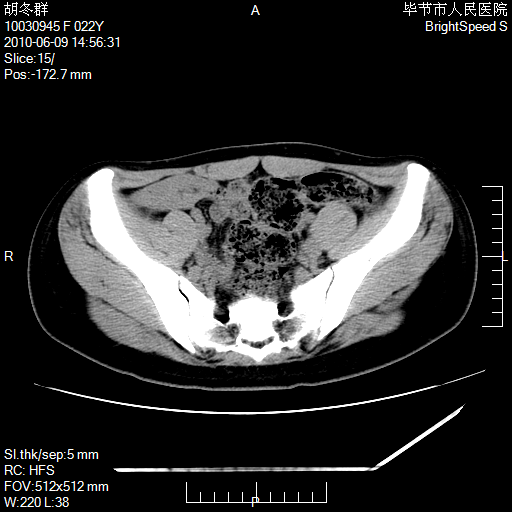

患者23岁,发现腹部包块3月。

左侧卵巢囊腺瘤或囊腺癌

盆腔内囊性占位性病变;考虑左侧卵巢囊腺瘤。

有分隔、壁薄,支持考虑左侧卵巢囊腺瘤。

左侧卵巢浆液性囊腺瘤。

支持考虑左侧卵巢囊腺瘤;宫腔积液。

有分隔、壁薄,支持考虑左侧卵巢囊腺瘤。排尿后,膀胱缩小,由于重力作用,肿块下移就到了膀胱位置,很好理解。